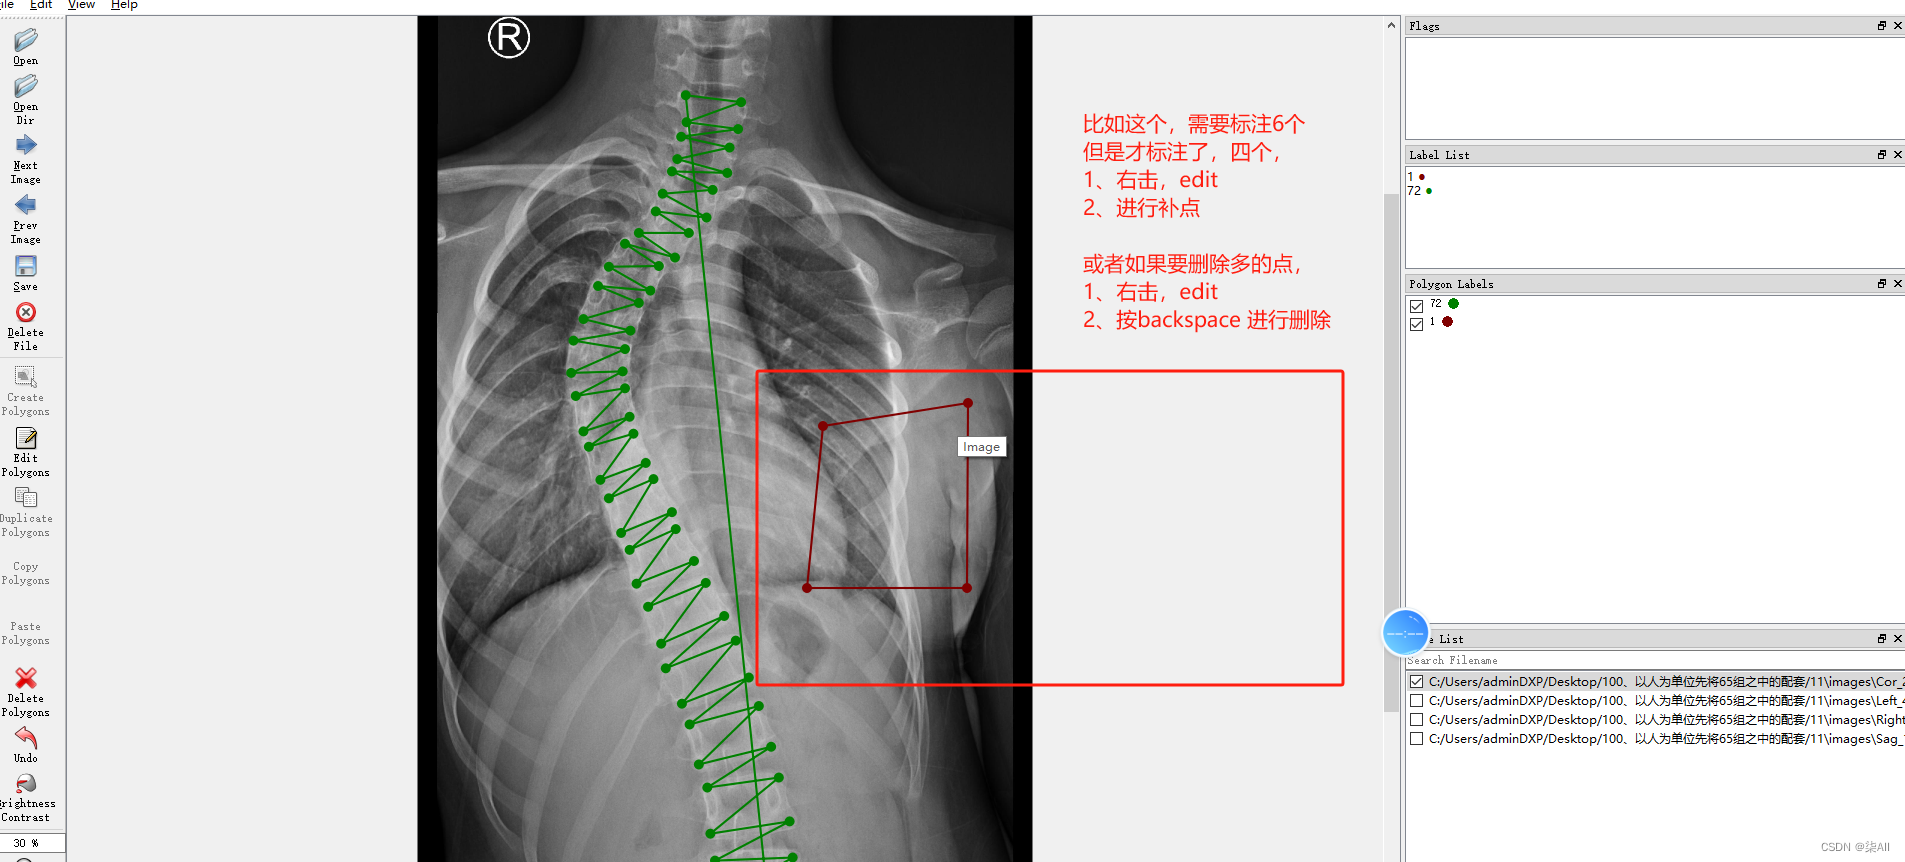

4.1、关键点不小心标注的位置不对

4.2 少标记或者多标记点。进行补点或者进行删除